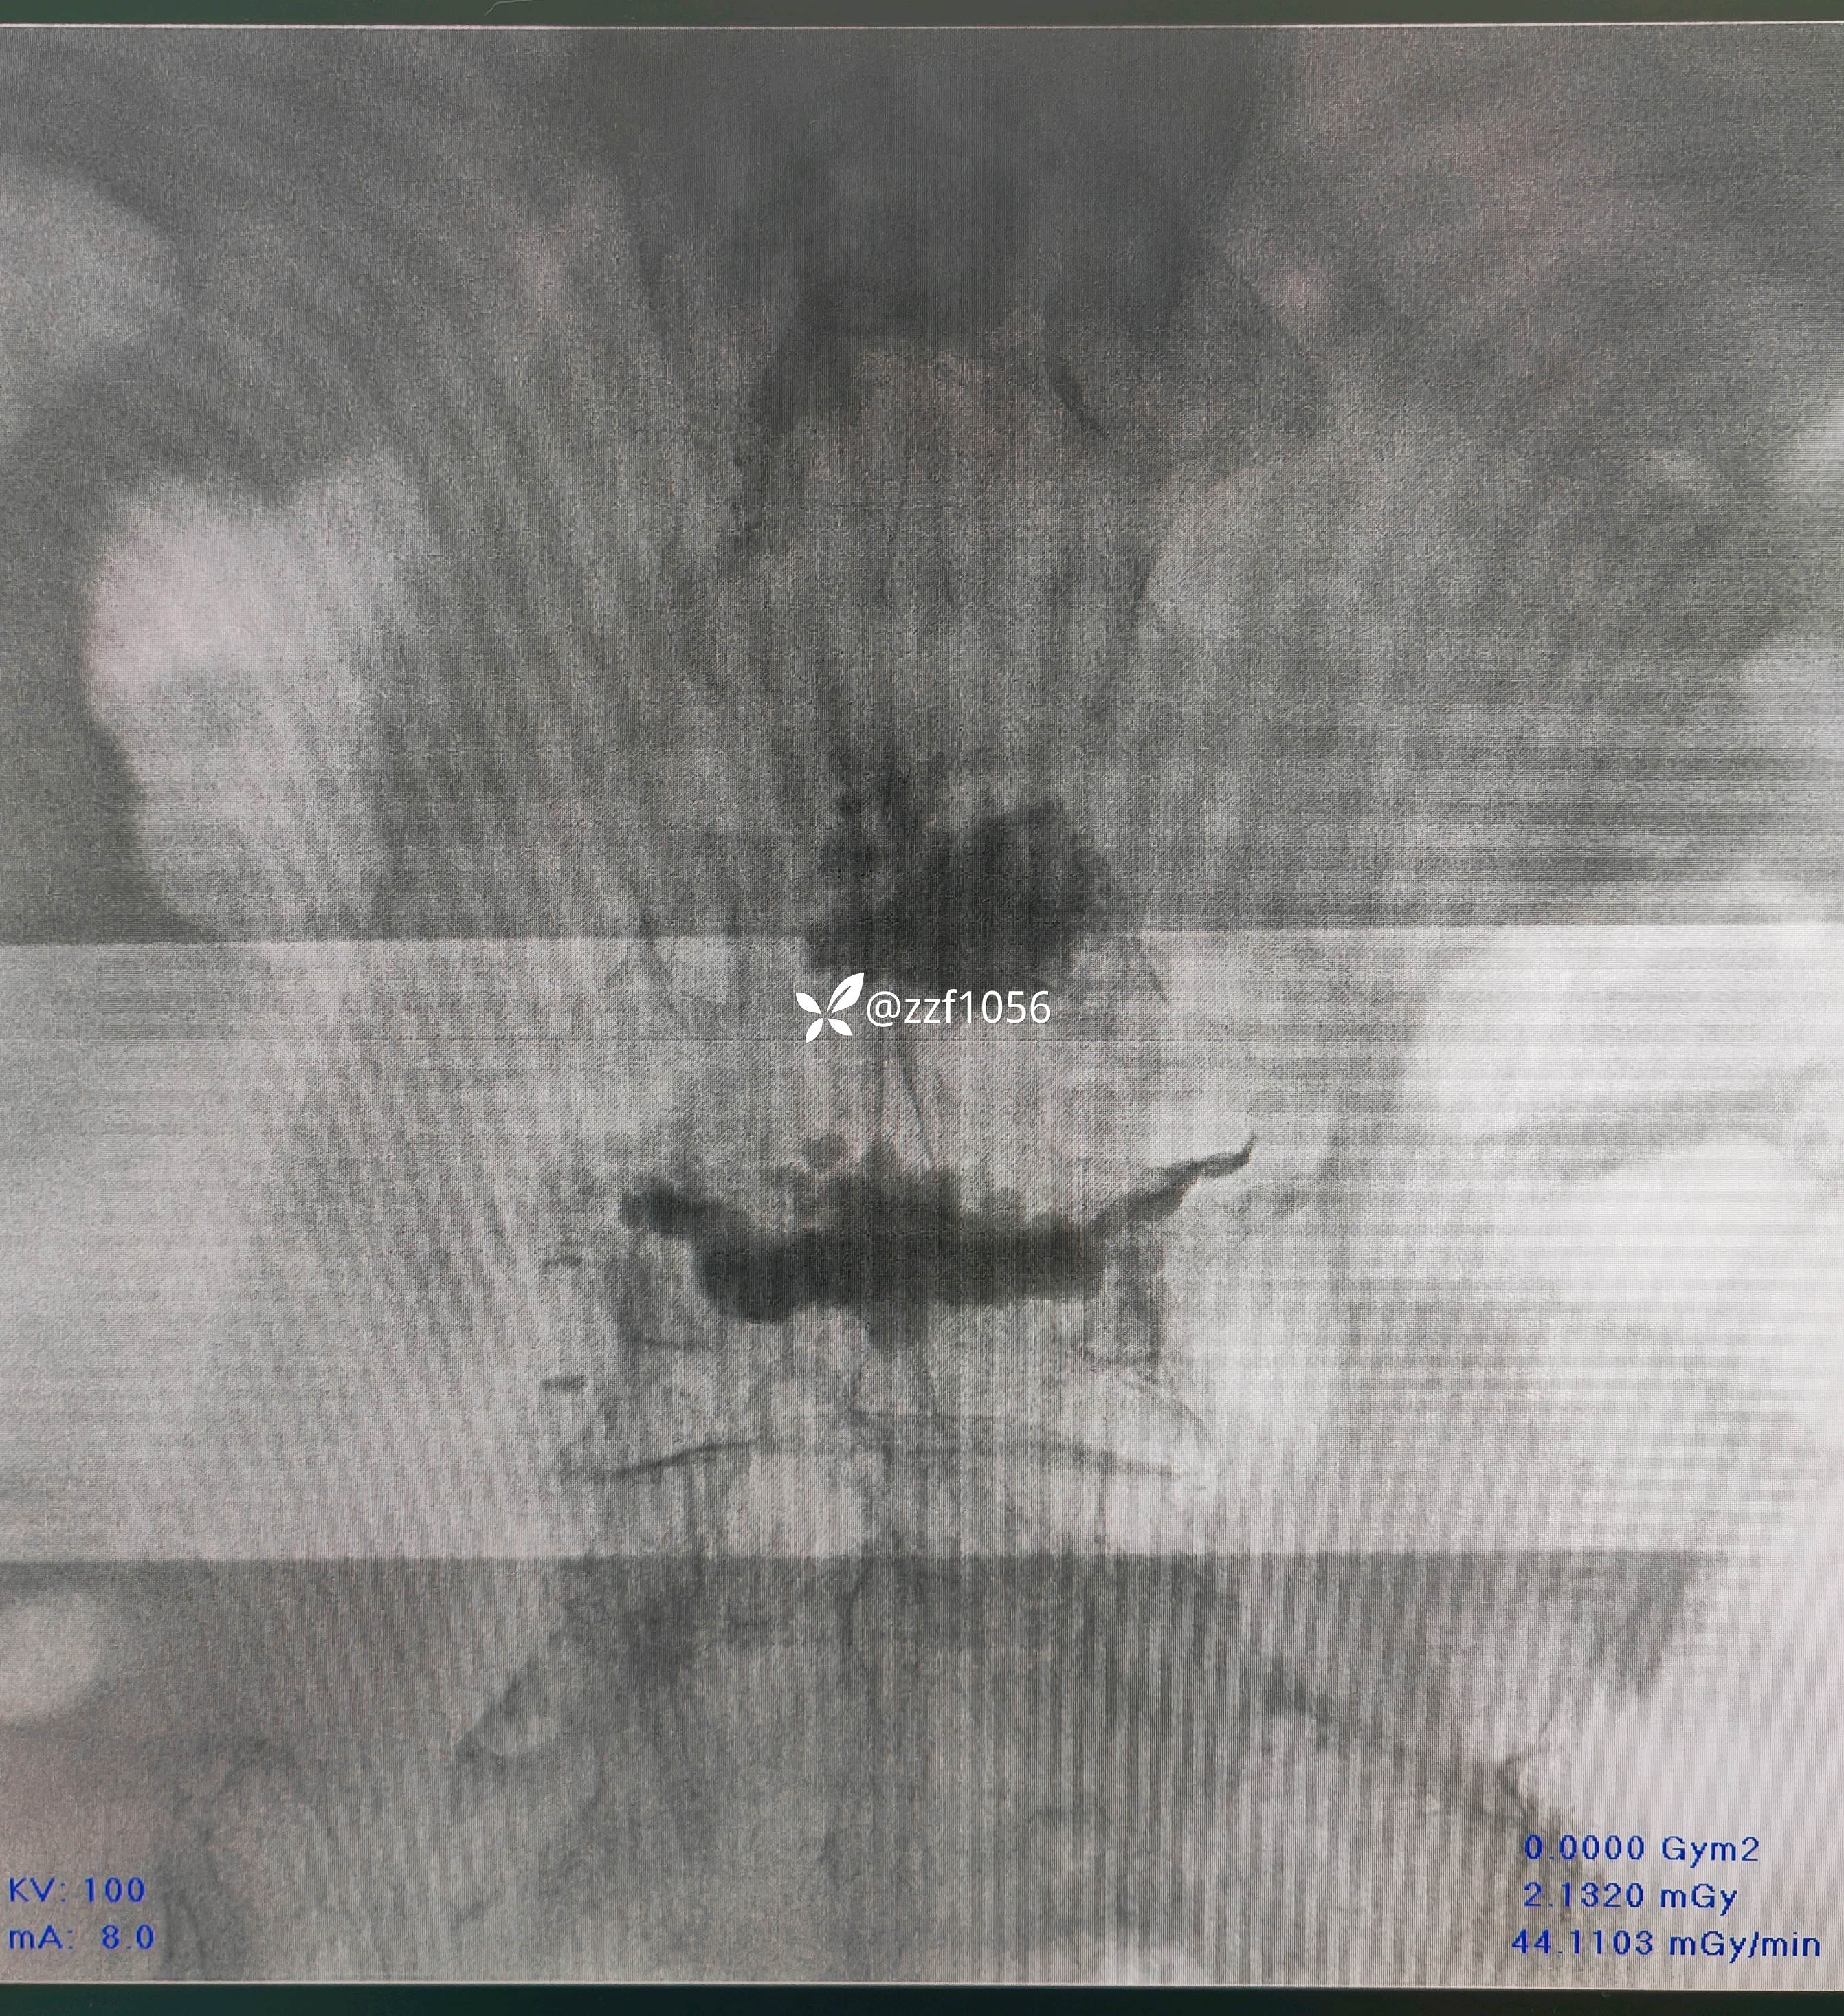

仔细一看这个侧位片,吓我一跳,骨水泥进椎管了?

果不其然,骨水泥渗漏入椎管内,非常能感受到当时主刀惊出一身汗😓,万幸的是患者并没有神经症状。